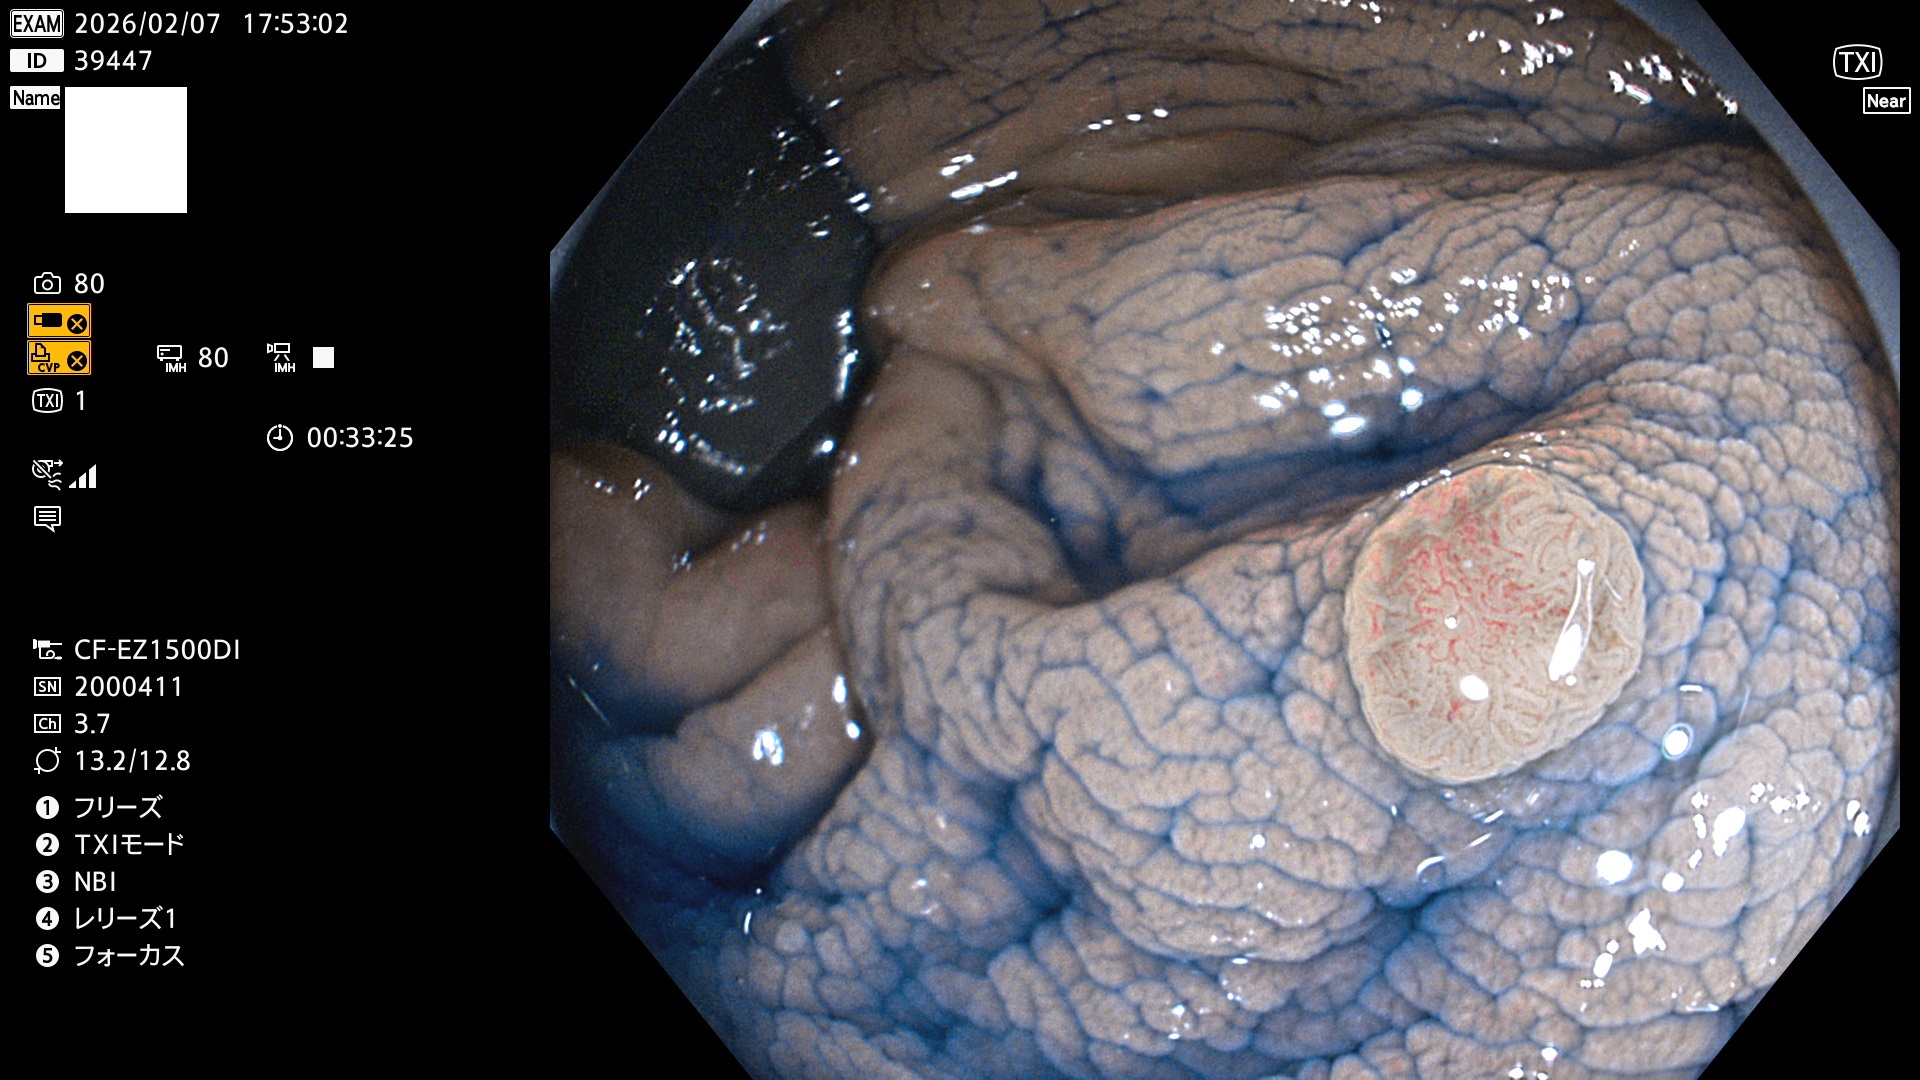

完全に平坦な物をUb、陥凹している物をUcと呼びます。Ubは認識が困難で、Ucはびらん(炎症)と紛らわしいために見落とされやすく、「内視鏡後・大腸癌」の原因になります。

専門的)細胞生物学的Ucの再定義UcをPitと形態学で定義するのは医学的には全く不毛です。Ucの本質はIntraTumor HeterogenityとTumor Dormancyが微小病変に見られる点です。これは早い腫瘍進化=ゲノム不安定性を意味します。そのような病変は隆起型でも形態によらずUcと定義すべきです。なぜなら1年後には陥凹し典型的Uc(最悪の場合NPG癌)になるからです。

毎週の検査(木・金・土・日)に発見されたUbとUc型・腺腫を、その週の日曜の夜にUPし1週間、提示します。

2026年2月5日〜2月8日の4日間(40件)で9個 (Uc_ADR=9個/40人=23%)